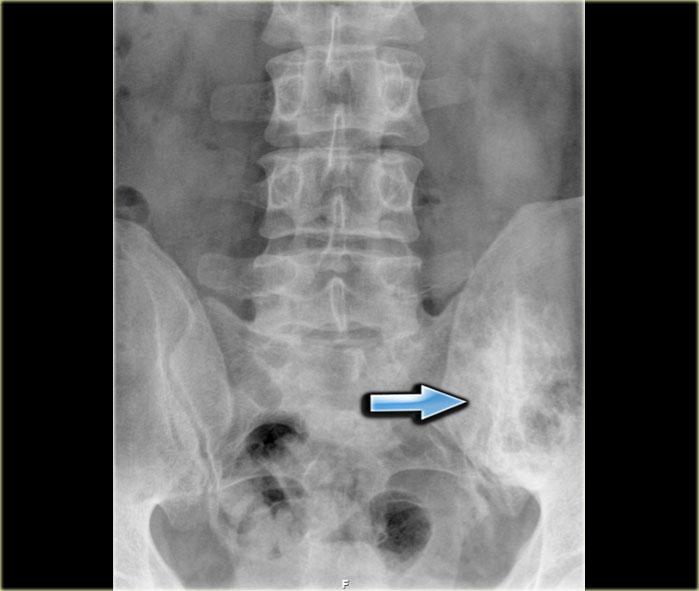

Đây là hình ảnh của một bệnh nhân ung thư tuyến tiền liệt.

Lưu ý các di căn xương chủ yếu là tạo xương (osteoblastic) với số lượng nhiều.

Đây là hình chụp X-quang vùng chậu với một ổ di căn tạo xương hầu như không nhìn thấy ở xương chậu trái (mũi tên xanh lam).

Lưu ý rằng CT mô tả các tổn thương này rõ hơn nhiều (mũi tên đỏ).